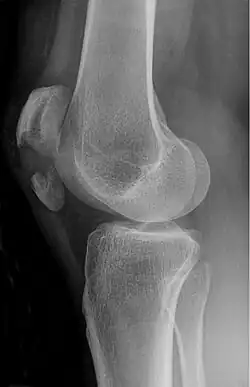

-

Comminuted fracture of patella -

The patella can break in various ways depending on the way it is injured, and into two or more pieces.[1] Types include transverse, the most common, with one fracture line;[5] marginal; osteochondral; and the rare vertical type, or stellate, where a direct compression force gives rise to a comminuted pattern.[5][7] Patella fractures can be further classified as displaced, where the broken ends of bone do not line up correctly and separate by more than 2mm, or undisplaced and stable where pieces of bone remain in contact with each other.[1][7] If fragments of patella bone stick out from the skin it is known as an open patella fracture, and closed if the overlying skin is intact.[1]